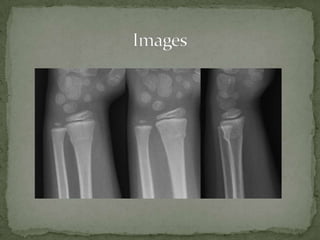

A 7-year-old boy presented with right arm pain after falling on an outstretched arm while playing. Examination revealed tenderness over the distal forearm with full range of motion of the fingers and intact neurovascular status. X-ray showed a non-displaced torus fracture of the distal radius. Treatment consists of splinting and a short arm cast for 3 weeks for comfort and prevention of further injury, with no reduction needed. Torus fractures are unique to children and occur when pediatric bone buckles rather than fully fracturing under axial loads.